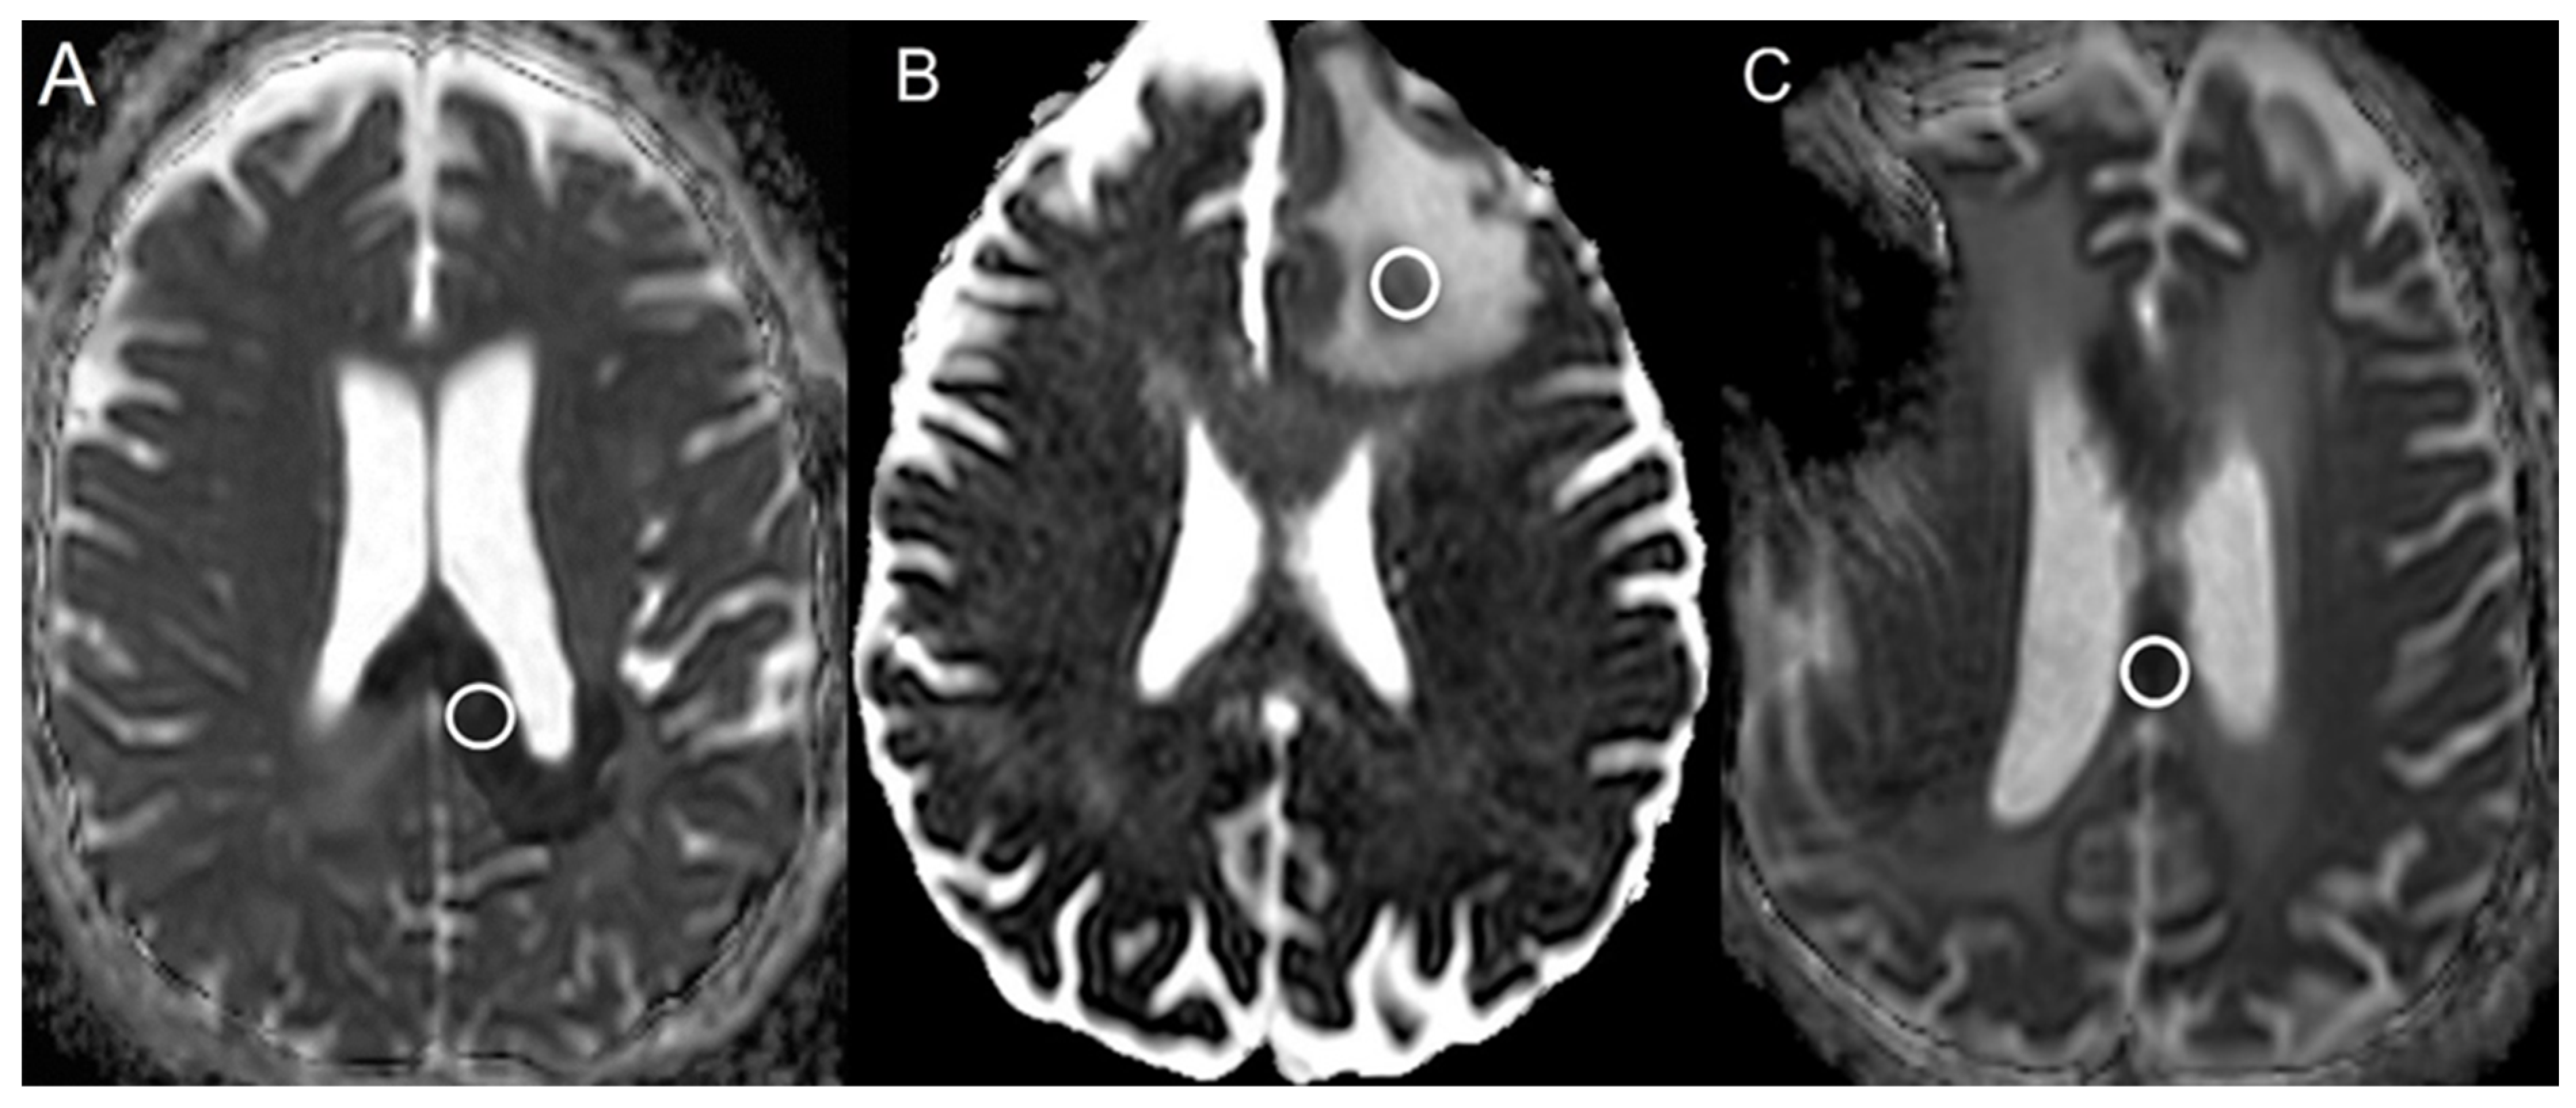

| Group | AUC | 95% CI |

|---|---|---|

| Bevacizumab | 1.00 | N/A |

| Progressive glioblastoma | 0.59 | 0.41–0.70 |

| Radiation necrosis | 0.98 | 0.95–1.00 |

| Group | N | Mean ± SD |

| Bevacizumab | 21 | 0.39 ± 0.10 |

| Progressive glioblastoma | 49 | 1.07 ± 0.22 |

| Radiation necrosis | 58 | 0.66 ± 0.14 |